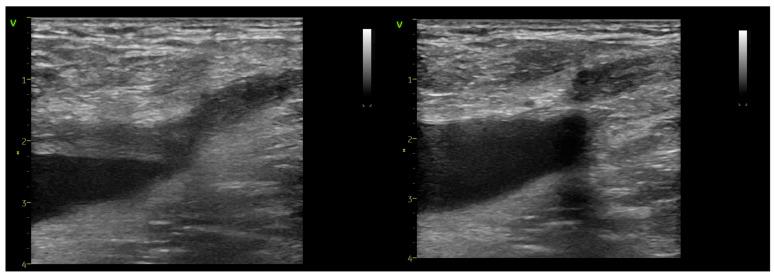

The introduction of radial-firing laser fibers has minimized catheter-to-vein distance during endovenous laser ablation (EVLA) for the great saphenous vein (GSV) and anterior saphenous veins (ASVs). This study investigates flush endovenous laser ablation (fEVLA) effectiveness in addressing chronic superficial venous insufficiency (CVI). This single-center retrospective study analyzed consecutive fEVLA cases with duplex ultrasound follow-up at 1, 4, and 12 weeks. The primary endpoint was clinically significant endovenous heat-induced thrombosis (classes III-IV). Three hundred and twelve patients were recruited (405 affected limbs, 369 GSV, and 36 ASV). CEAP classifications were stratified as follows: C2 in 6.1%, C3 in 34.2%, C4 in 44%, C5 in 2.7%, and C6 in 12.7% of cases. Perforator ligation, phlebectomy, or foam sclerotherapy were carried out in conjunction with EVLA. fEVLA was feasible in all cases. The success rate was 96.78%, defined as EHIT classes 1 and 2, and assessed by ultrasound one week postoperatively. Clinically significant EHIT (2.5% class 3 and 0.2% class 4) was managed with 15 mg rivaroxaban twice daily for 21 days. Follow-up at 4 weeks revealed complete resolution of all EHIT 3-4 cases. No cases of pulmonary embolism or deep vein thrombosis were observed during the study or follow-up period. fEVLA is a safe treatment for superficial CVI across various CEAP classes, and with prompt detection, the minimal complication rate can be completely resolved.

径向发射激光光纤的引入,已将大隐静脉(GSV)和前隐静脉(ASV)腔内激光消融术(EVLA)期间导管与静脉的距离降至最低。本研究调查了冲洗式腔内激光消融术(fEVLA)治疗慢性下肢浅静脉功能不全(CVI)的有效性。这项单中心回顾性研究分析了连续接受fEVLA治疗且在1周、4周和12周进行双功超声随访的病例。主要终点是具有临床意义的腔内热诱导血栓形成(III-IV级)。共纳入312例患者(405条患肢,369条GSV和36条ASV)。CEAP分级分层如下:C2级占6.1%,C3级占34.2%,C4级占44%,C5级占2.7%,C6级占12.7%。在进行EVLA的同时进行了交通静脉结扎、静脉切除术或泡沫硬化疗法。fEVLA在所有病例中均可行。成功率为96.78%,定义为EHIT 1级和2级,术后1周通过超声评估。对于具有临床意义的EHIT(2.5%为3级,0.2%为4级),给予利伐沙班15 mg,每日两次,共21天。4周随访显示所有EHIT 3-4级病例均完全消退。在研究或随访期间未观察到肺栓塞或深静脉血栓形成病例。fEVLA是一种治疗各种CEAP分级的浅表CVI的安全方法,并且通过及时检测,可将最低并发症发生率完全解决。